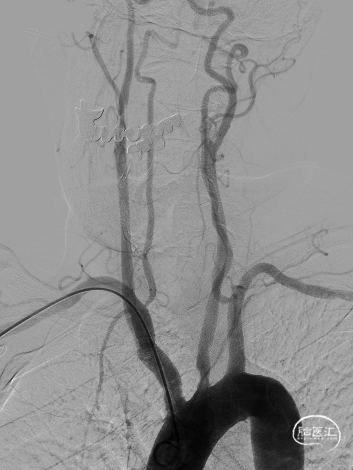

➢ 脑血管造影检查

患者主因言语不利3天入院,头核磁提示右侧额、顶叶多发低灌注梗塞,脑血管造影提示右侧颈内动脉开口重度狭窄,为责任血管,另外患者前交通动脉、右侧后交通动脉开放不良,并且狭窄严重,考虑到高灌注风险,决定分期处理,一期小球囊扩张改善供血,二期支架成型。